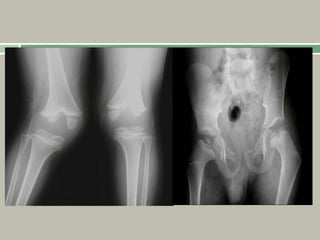

Radiographic findings

Synchronous and symmetric involvement of the femoral

epiphyses, without development of lucencies,

differentiates this from Perthes disease.

The femoral heads become flattened and enlarged, which

may result in hip subluxation.

Knees can demonstrate varus or valgus malalignment.

Delayed appearance of the epiphyses (femoral heads

appear age 5 years),

Flattened irregular epiphyses,

Platyspondyly, possibly with a kyphoscoliosis,

Odontoid hypoplasia,

Atlantoaxial instability may be seen on flexion or

extension views,

Coxa vara, if severe, may result in femoral neck

discontinuity.

1, 2: Odontoid

hypoplasia and subtle anatomic axis

instability.

4:Pelvis, delayed ossification and irregular

epiphyses of the hips with overgrown

trochanters.

Fairbank’s triangle is present

3,5: Kyphoscoliosis with irregular vertebral

epiphyses.

Platyspondyly (flattened vertebral bodies) is

evident in lumbar spine